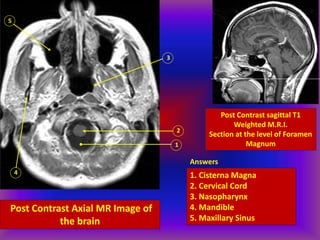

Post Contrast Axial MR Image of

the brain

1

2

3

4

5

Post Contrast sagittal T1

Weighted M.R.I.

Section at the level of Foramen

Magnum

Answers

1. Cisterna Magna

2. Cervical Cord

3. Nasopharynx

4. Mandible

5. Maxillary Sinus